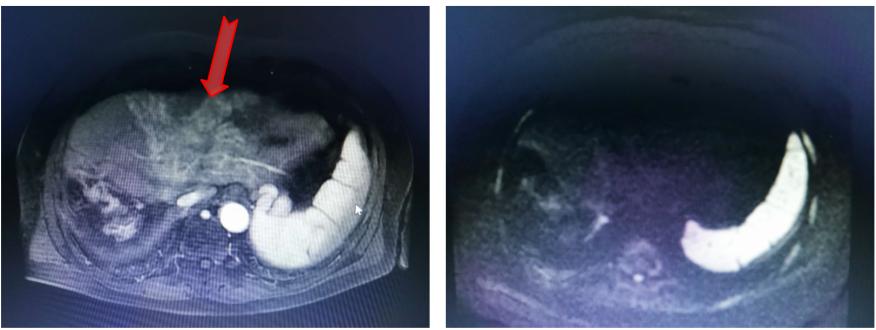

随后患者定期复查,并开始口服仑伐替尼治疗。因乏力、纳差等不良反应,患者服药2月后拒绝继续服用,停药观察。AFP持续升高。2017年底患者开始服用瑞戈非尼治疗。AFP出现短暂下降,2018年2月初AFP再次反弹。复查MR提示左叶可疑病灶(图6)。

图6. 靶向治疗后腹部MR

2018年1月开始在瑞戈非尼基础上加用纳武利尤单抗100 mg q2w。AFP出现短暂降低后继续上升,2018年3月到达整个治疗过程的最高值65.8 ng/ml,随后AFP出现断崖式下降,1个半月后降到正常范围。使用纳武利尤单抗2个月后复查MR,提示DWI无明显高信号,可能为放疗联合免疫治疗导致的肝损伤(图7)。2018年6月至今AFP波动在0.86 ng/ml~1.90 ng/ml之间。治疗全程AFP变化情况见图8。

图7. 免疫治疗2个月后腹部MR